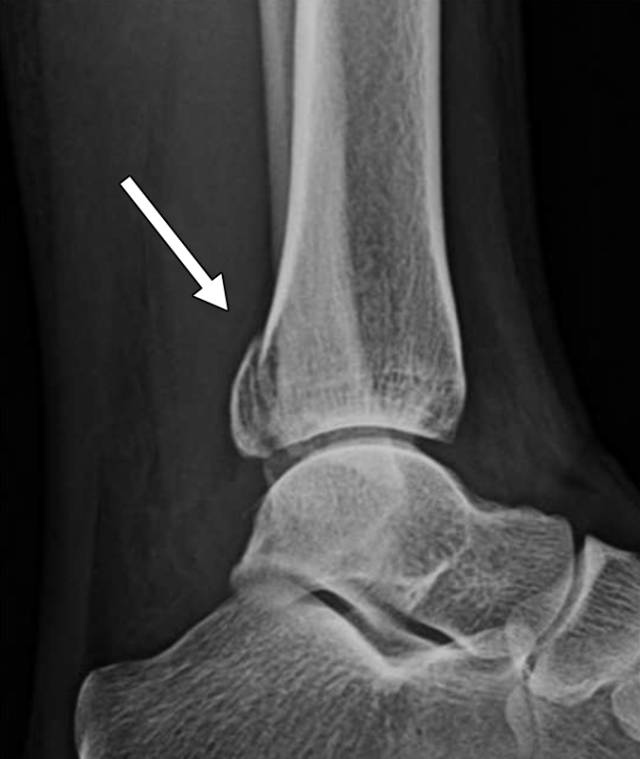

在膝关节处,髌骨的骨折可能不明显,除非获得轴向髌骨视图(图1)。缺乏体重视图可导致跗横关节或跗跖关节(Lisfranc or Chopart joint)损伤的假阴性射线照相结果[5,6]。压力观察可能是必要的,以显示对踝臼或下胫腓分离

图1〜20岁的男性患者出现短暂的外侧髌骨脱位。骨折在侧位和前后位X线照片上不可见。轴位视图显示沿着髌骨的中间边缘的多个撕裂碎片(箭头)。